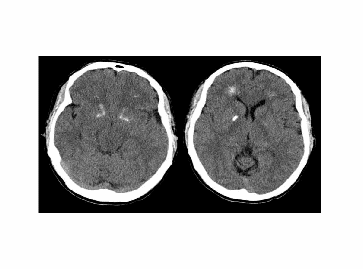

При морфологическом исследовании мозга и ЯМР-томографии могут наблюдаться (примерно в 12% случаев) кисты червя мозжечка, аномалии коры головного мозга.

Рис. 1. 15 хромосома

Рис. 9 Компьютерная томограмма мозга пациента с делецией